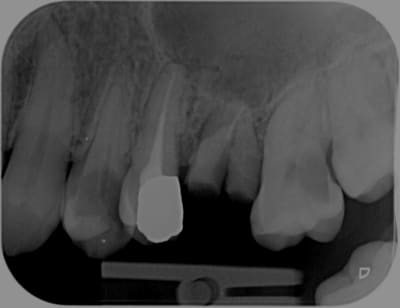

Ben voilà:

For English speaking folks:

E a versão Português, Acabado o Cerec !:

encore une:

Voco va faire des affaires !